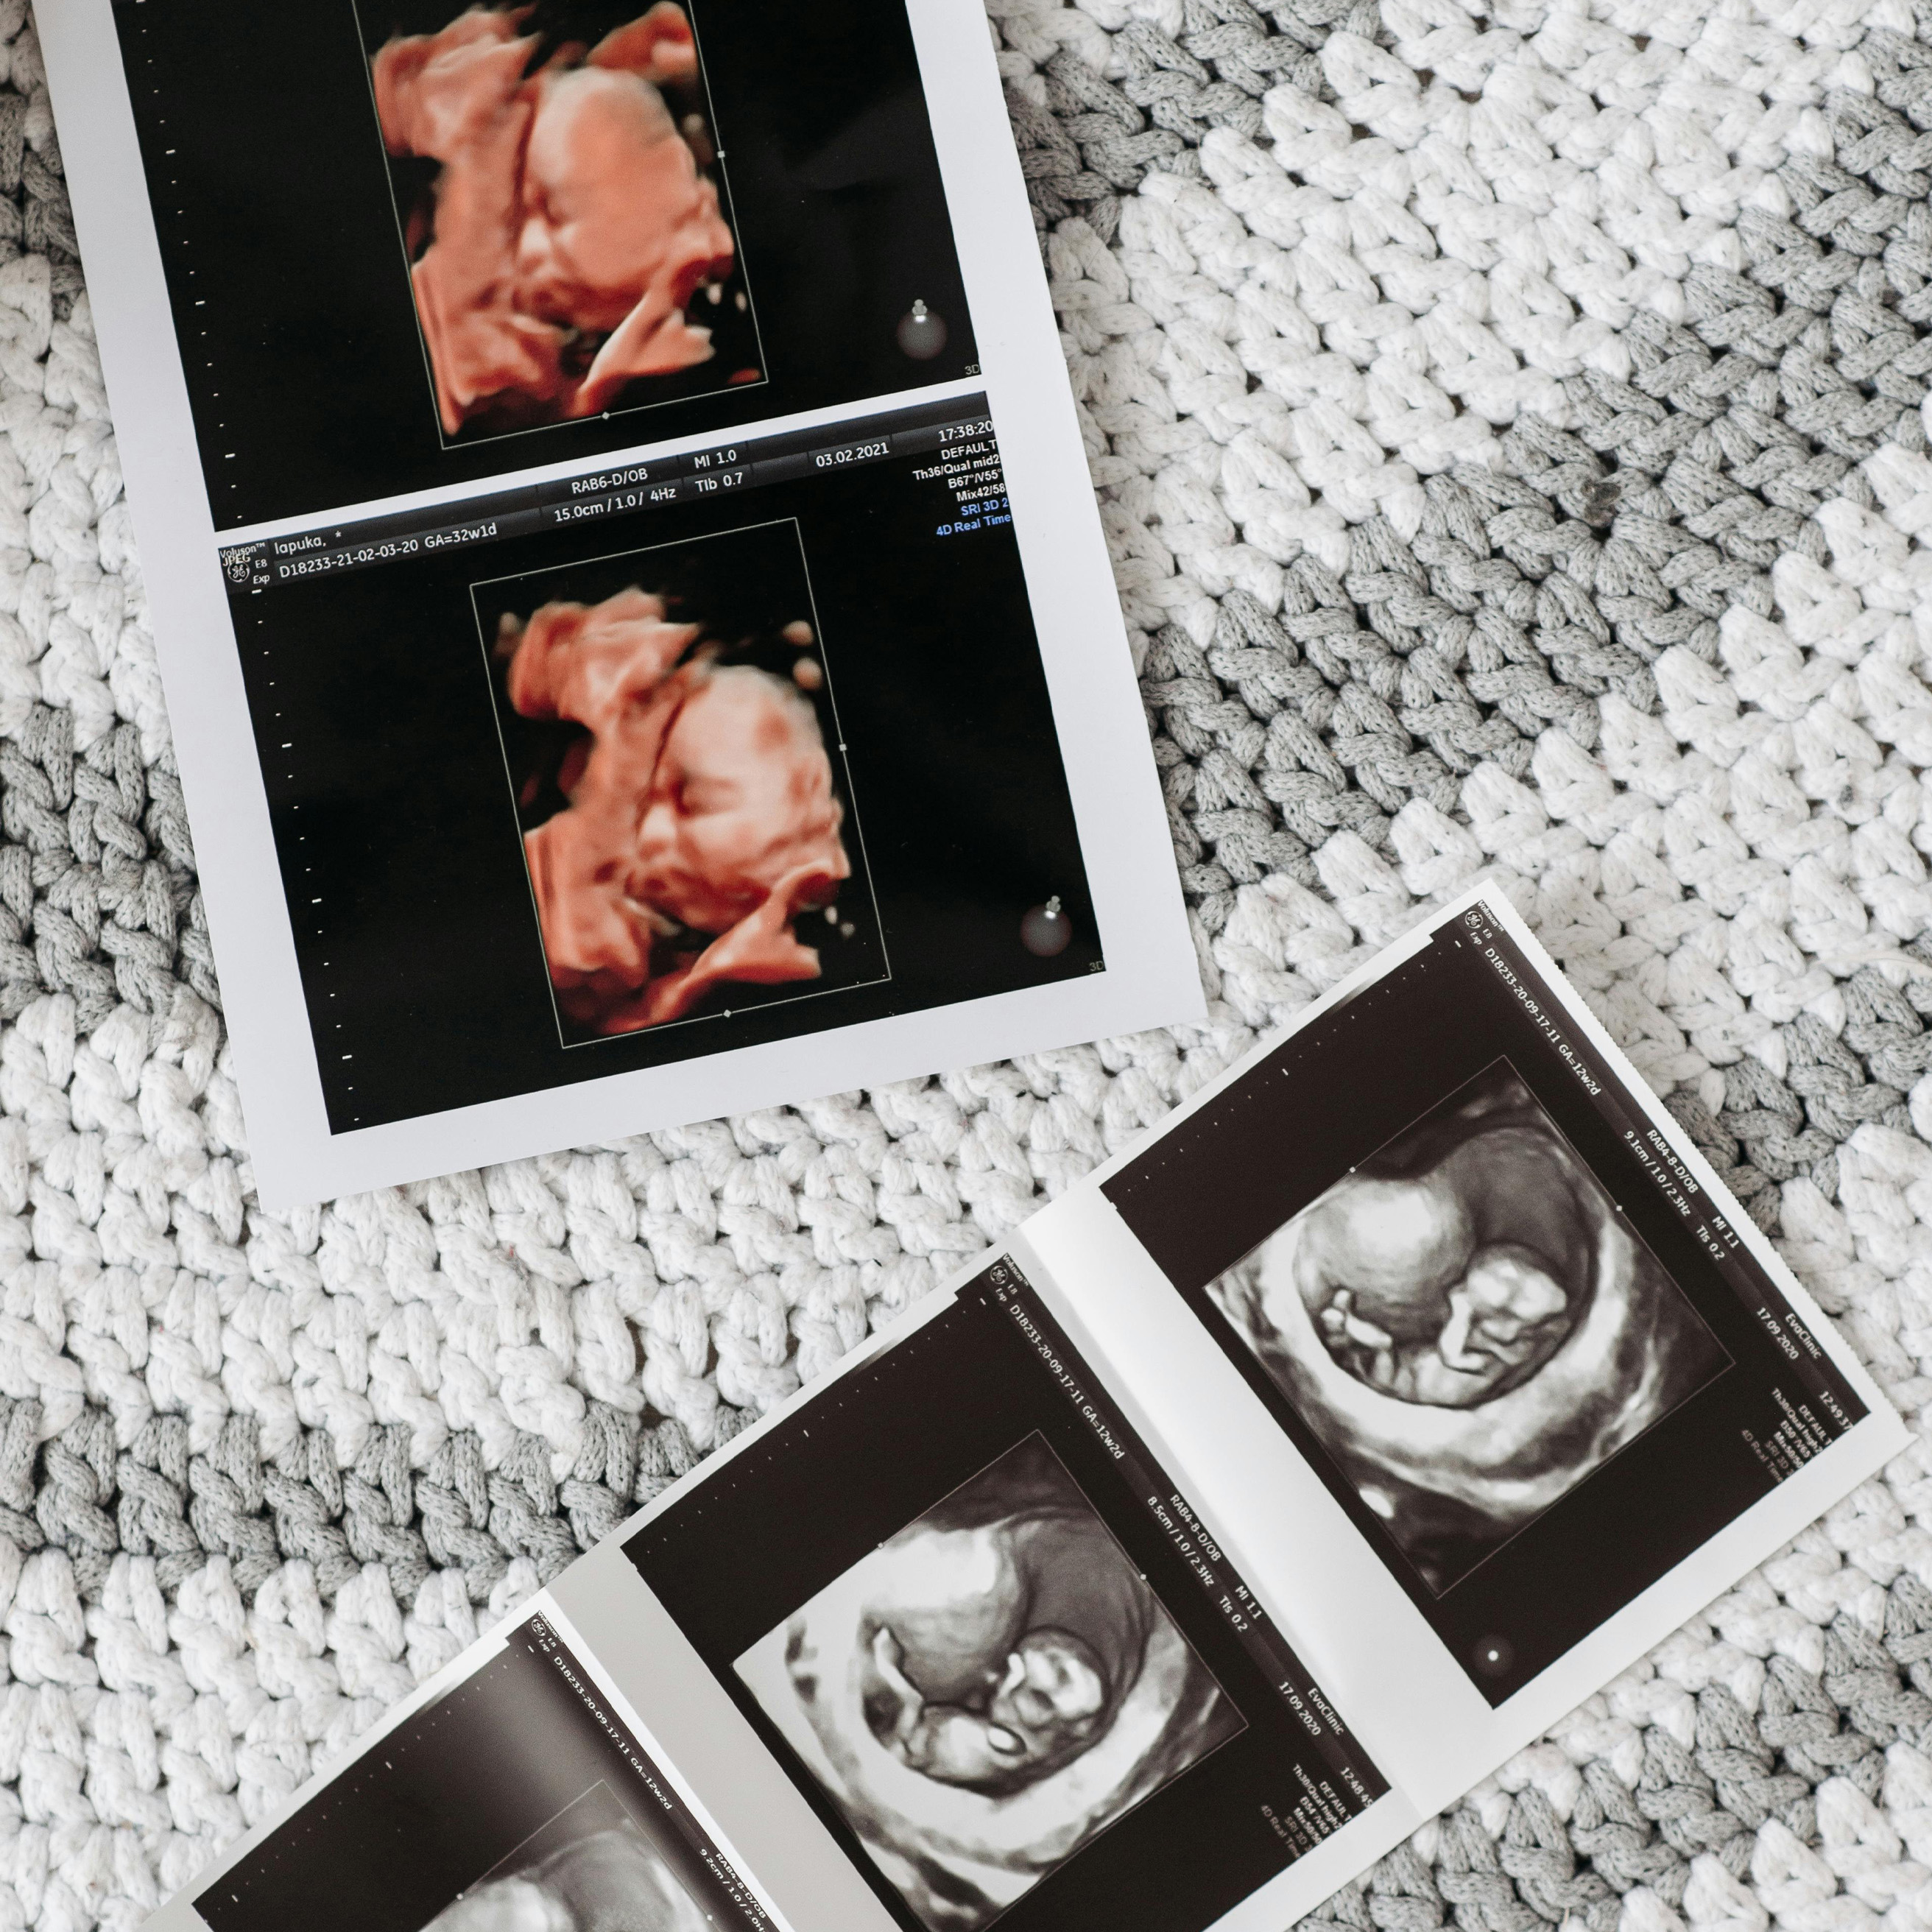

Ecografías Medicina Fetal

• Ecografía Obstétrica

• Ecografía de Marcadores de Aneuploidias

• Ecografía Obstétrica Morfológica